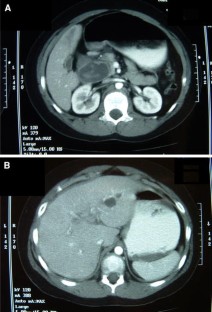

Choledochal cysts are rare, congenital malformations of the intra and/or extrahepatic biliary tree. We describe a case in which a patient was transferred to our hospital with a reported duodenal hematoma. The patient ultimately required exploration when his condition deteriorated. Laparotomy resulted in the discovery and successful treatment of a ruptured type IV-A choledochal cyst.

Fig. 1